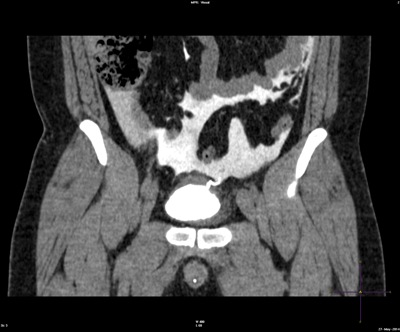

A 45-year-old male presented with acute onset abdominal pain following a fall whilst out drinking.

A CT cystogram was arranged as he developed haematuria and acute renal impairment.

1. Intra-peritoneal bladder perforation (note contrast leaking into peritoneal cavity and defect in bladder).

2. Catheterise patient: 300-400mls of dilute (50:50) water soluble contrast is installed into the bladder via gravity. Films are taken in early filling phase, full bladder (AP, oblique and posterior) and post void stage.

3. Intraperitoneal (30-40%), extraperitoneal (50-60%) or combined intra-extraperitneal (5-10%).

4. Uncomplicated extraperitoneal rupture can be safely managed by catheter drainage alone. Surgical intervention may be necessary for bladder neck involvement, the presence of bone fragments in the bladder wall, or concomitant rectal injury. Catheter drainage for 7-14 days, with a cystogram prior to catheter removal. Intraperitoneal rupture should be managed by formal surgical repair. Other abdominal organs should be inspected and urinomas drained. Operative repairs of the bladder should be performed by a two layer closure (mucosa and detrusor) with absorbable sutures. Cystogram should be performed before catheter removal.